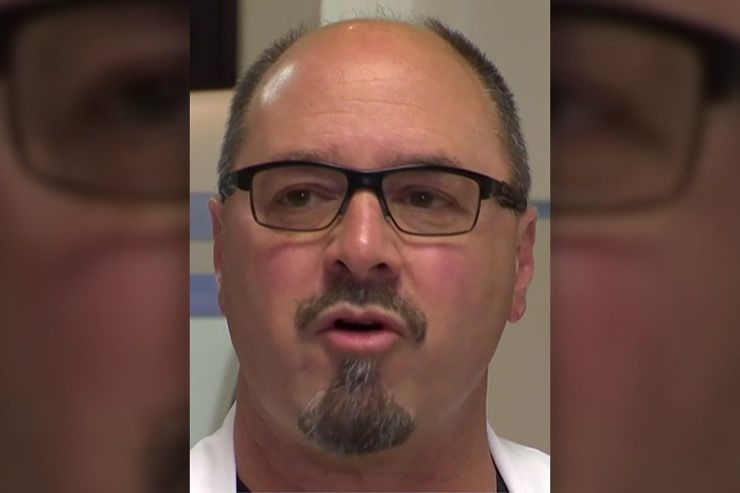

Worrying Condition

Cardiologist Dr. Gary Fazio was on call when Ed Burkett was brought in. He recalled that by the time Burkett actually arrived in the emergency room, he looked awful. Over the next harrowing hour, this particular patient would prove to even a veteran physician like Fazio what the human body is capable of.

A Near Thing

It was a near thing to the end and one that Dr. Fazio considers nothing short of miraculous. “There are miracles that happen every day here,” he explained while talking to NBCDFW. The astonished doctor added that “Sometimes it takes someone like Ed to make it so obvious.” The incident wasn’t just miraculous, it was also unheard of.

44 Attacks, 20 Years

Dr. Fazio had been in medicine for more than 20 years and in two decades of working with patients and specifically the heart, he had never seen someone survive after 44 separate attacks. He had never come close to witnessing that kind of physical and emotional fortitude. “Generally speaking, after that many defibrillations, you’ve lost that battle,” he explained.

Great For Everyone

Dr. Fazio said that Burkett’s amazing story has lifted the spirits of staff and patients alike in his hospital. His story of survival is a reminder that where there is life, there’s hope. He adds that “if you have faith, anything is possible.” But Burkett is hardly the first cardiac patient to defy the odds in recent years.